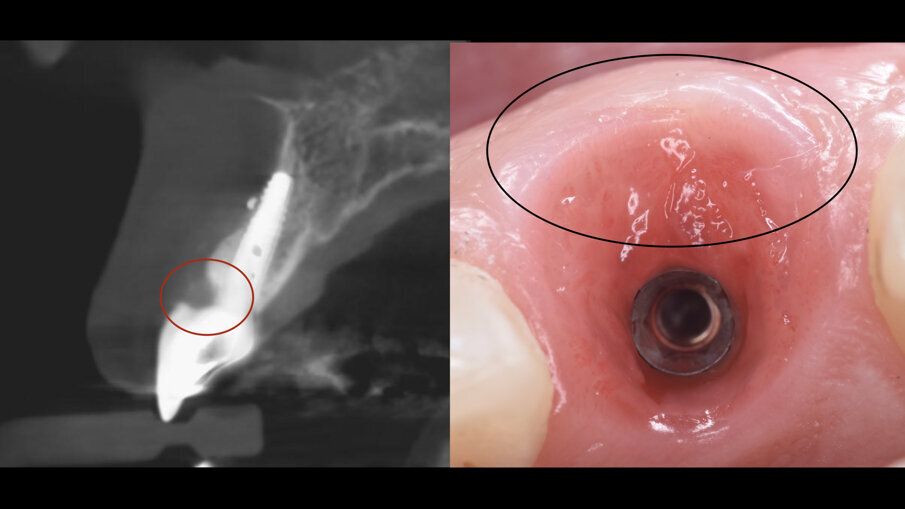

All’esame obiettivo generale la paziente presenta una malocclusione di 2a classe con recessioni multiple dei settori frontali e lateroposteriori, un sorriso gengivale e un fenotipo gengivale sottile e festonato con denti di forma triangolare, mentre a livello locale il dente 1.1 si presenta fortemente discromico con fistola apicale, recessione dei tessuti molli sia del 1.1 che del 2.1 di circa 3 mm con erosione cervicale (Fig. 2). Una prima indagine radiografica bidimensionale (rx endorale periapicale) evidenzia sul 1.1 una terapia canalare incongrua e radiotrasparenza apicale. Un esame tridimensionale CBCT evidenzia la discontinuità della corticale vestibolare identificata come classe 4 secondo Tarnow4, come esito dell’infezione apicale, ma rimane un ponte osseo crestale che sarà fondamentale per il percorso di ricostruzione dei tessuti duri e molli (Fig. 3).

La paziente è stata dimessa con terapia farmacologica di supporto e a due settimane si è proceduto alla rimozione delle suture riassorbibili e i controlli clinici sono stati eseguiti poi a 1 mese, 3 mesi e 5 mesi. Al termine della fase di maturazione dei tessuti (5 mesi) (Fig. 7) si è evidenziato come da un punto di vista clinico siano stati mantenuti i volumi sul piano verticale (addirittura più coronali di circa 2 mm rispetto al centrale contro-laterale 2.1) e sul piano trasversale vestibolo palatale, e inoltre il nuovo esame CBCT evidenziava la ricostruzione della parete ossea vestibolare (Fig. 8).